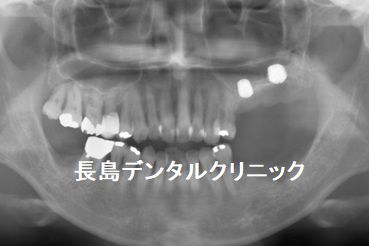

2、抜歯と同時にインプラントを埋入

人工骨を一切使用せず、エキストラワイドのショートインプラントを

埋入。

3、かぶせ物の装着